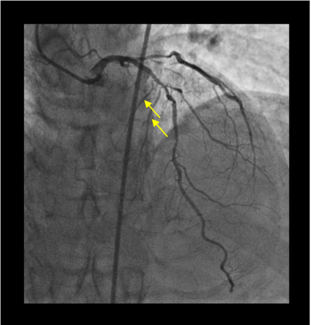

A 62-year-old man with a history of coronary artery bypass graft was referred because of worsening anginal symptoms despite being on optimal antianginal medical therapy. Physical examination, electrocardiogram, echocardiogram, and routine...